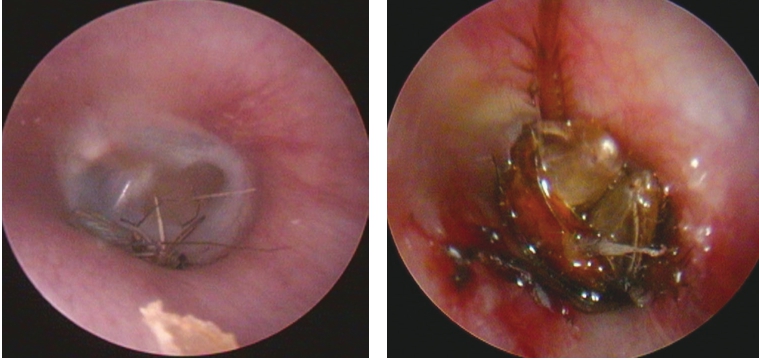

3.若外耳道内异物为活昆虫,可先滴入液体石蜡或丁卡因溶液等使昆虫固定、麻痹或死亡,然后用吸管、镊子或鳄鱼钳取出(图5-4)。

图5-4 麻痹或死亡昆虫可